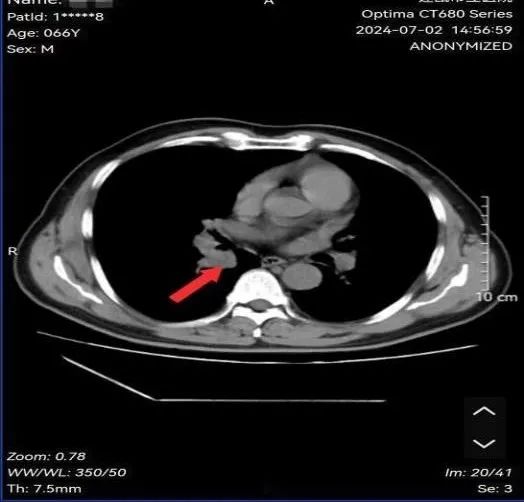

魏先生,男性,66岁,有长期吸烟史20余年,因反复咳嗽数月求诊我院,经肺部CT、支气管镜等检查确诊小细胞肺癌。经肺癌多学科诊疗小组专家会诊:建议完善骨ECT、脑部MRI检查后明确分期为:局限期小细胞肺癌,建议行同步放化疗治疗。

图为:治疗前病灶影像及病理结果